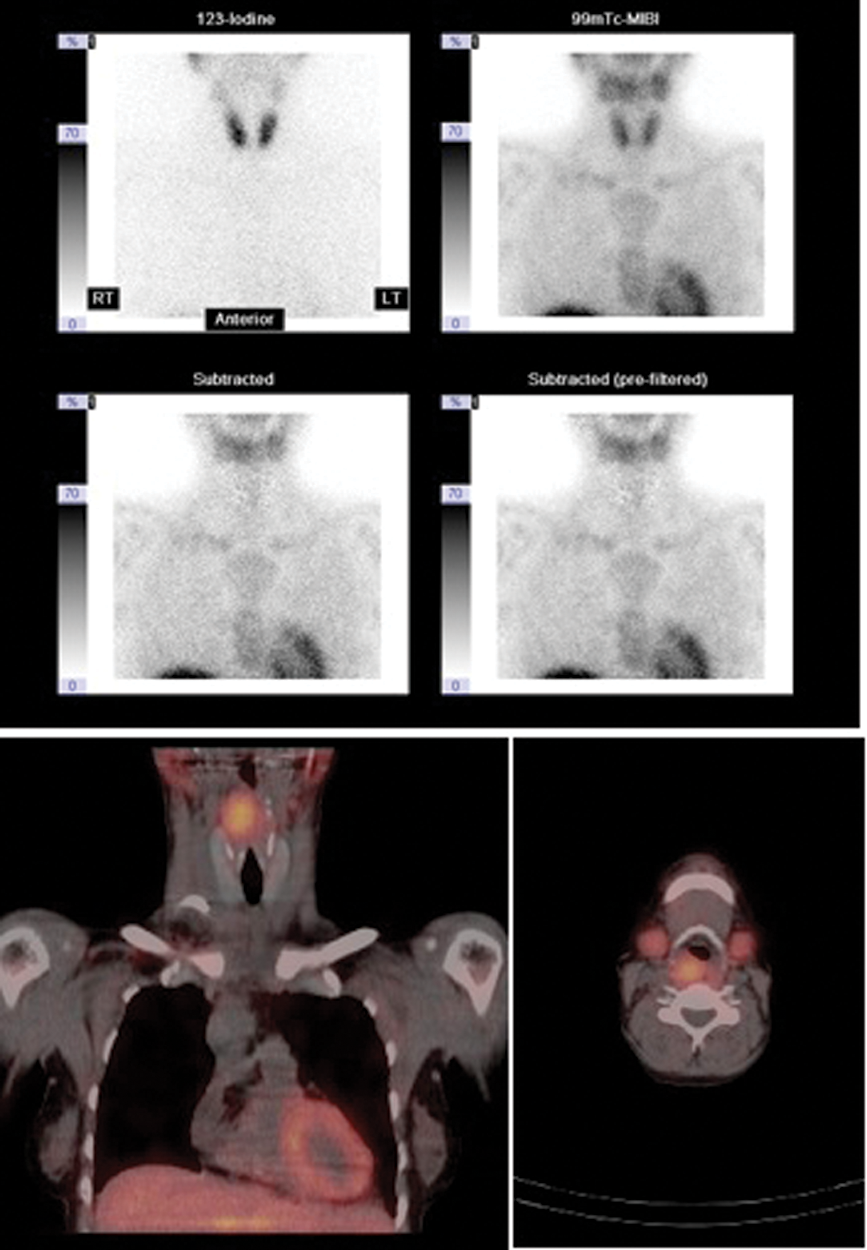

Figure 1: 123I 99mTc MIBI subtraction imaging with SPECT CT fusion. The planar subtraction images (top) show no convincing uptake however the subtraction SPECT CT fused axial (bottom right) and coronal (bottom left) images demonstrate retropharyngeal activity consistent with ectopic adenoma in the right posterior pharyngeal wall.

Functional imaging with scintigraphy demonstrates gland hyperfunction and can identify single or multigland disease. Imaging is hampered by relatively poor spatial resolution although single-photon emission computed tomography (SPECT) may be used to aid localisation (Figure 1). Scintigraphic techniques involve either subtraction or differential washout techniques. In the former, images demonstrating thyroid alone are subtracted from images demonstrating thyroid and parathyroid together to identify abnormal parathyroid tissue. Early subtraction techniques generated an image using thallium 201 (which is taken up by both thyroid and abnormal parathyroid tissue) and subtracted an image obtained using 99mtechnetium-pertechnate (99mTc-pertechnate) which is selectively taken up by thyroid (and salivary) glands. Literature reports demonstration of 72% of primary parathyroid adenomas but only 43% secondary adenomas using this technique [6].

However, relatively long imaging times of up to 20 minutes are required which may result in movement artifacts. More recently, 99mTc-sestamibi has been used in functional parathyroid imaging (Figure 2). This is taken up by both thyroid and by abnormal parathyroid tissue, and the radiopharmaceutical may be used for either subtraction or differential washout techniques with reported sensitivities of 88% for solitary adenomas [6]. Sestamibi subtraction imaging is used in conjunction with either 99mTc-pertechnetate or 123iodine to identify the thyroid gland. Washout methods utilise the differential clearance rate of sestamibi from thyroid and parathyroid tissue - washout from the thyroid is rapid compared to delayed washout in abnormal parathyroid tissue. The technique is simple, relatively quick and only uses one tracer but small or rapidly clearing adenomas may be missed [6].